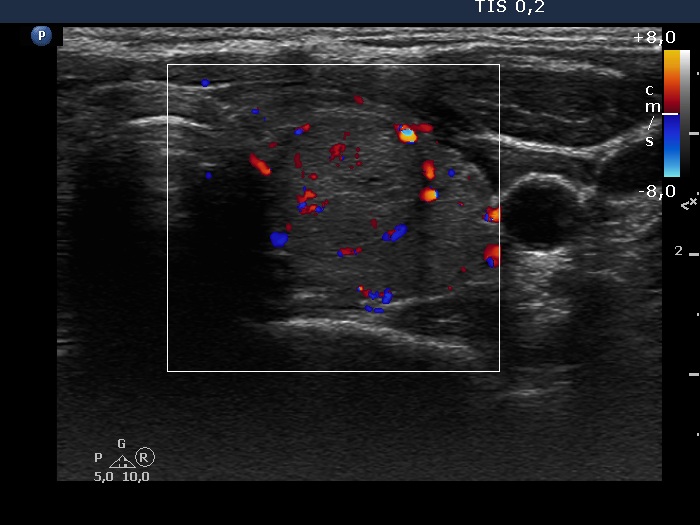

Discrete lesion or nodule in Hashimoto's thyroiditis - case 10 (95)

Follow-up investigation 38 months after the first visit (ultrasonographic picture 7)

Left lobe, transverse scan, color Doppler mode. The lesion presents signs of perinodular blood flow.